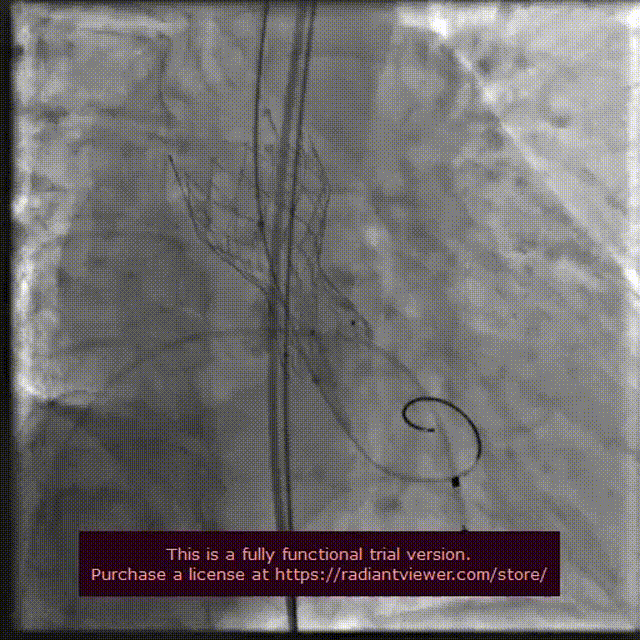

主动脉根部造影

18 mm球囊预扩

输送系统定位

VenusA-Plus®释放过程

18 mm球囊后扩

瓣膜完整形态

术者团队观察到瓣膜形态未能完全伸展,为取得更好治疗效果,后续予以后扩处理。采用18 mm球囊进行后扩后扩,行主动脉造影提示瓣膜置入位置良好、形态完整。